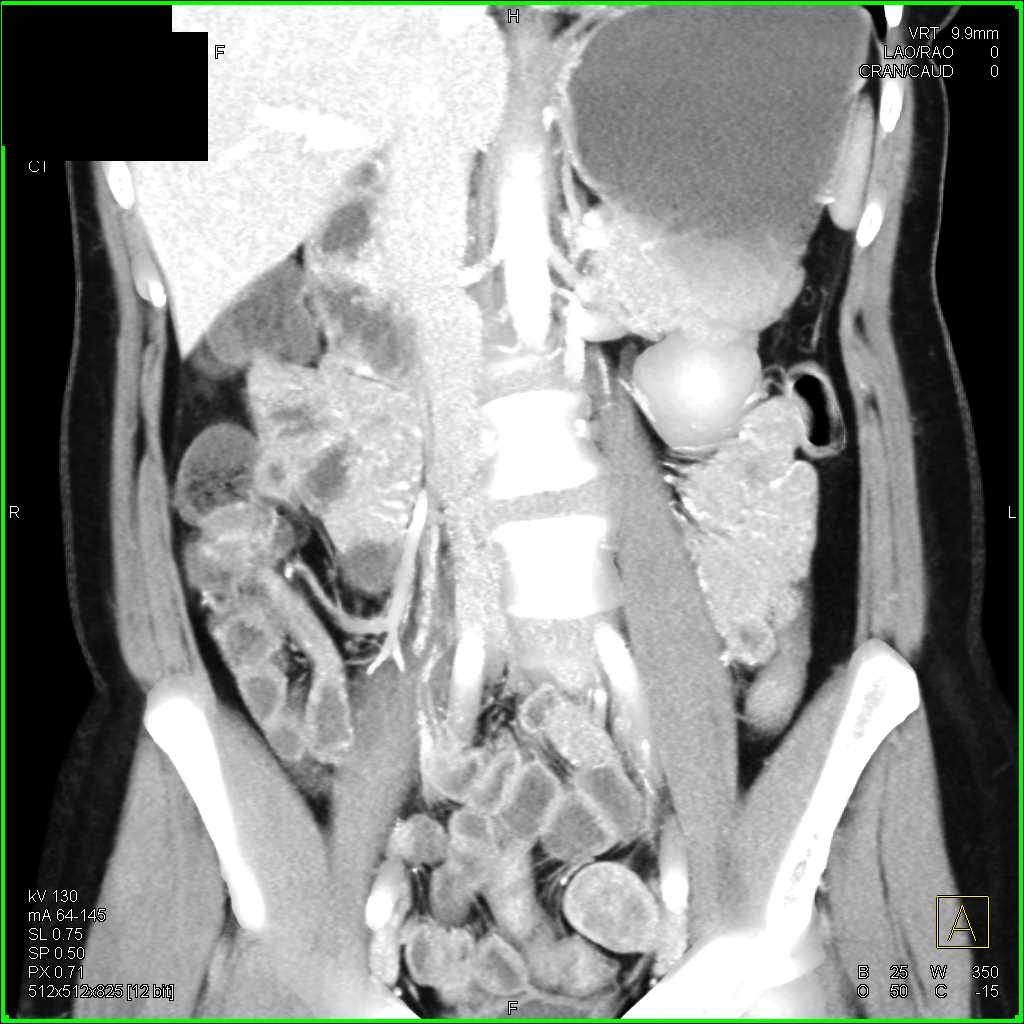

Crohns Disease Terminal Ileum